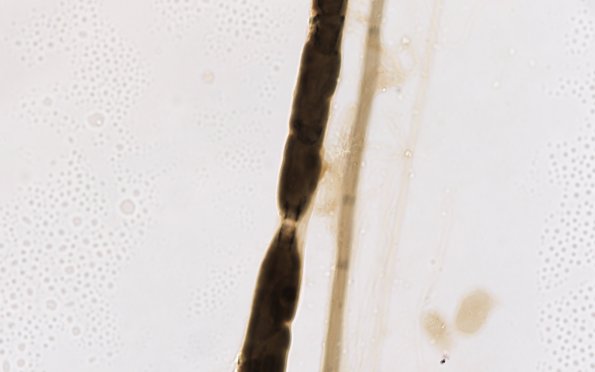

High magnification image of a node of Ranvier adjacent to a demyelinated axon. (Teased fiber preparation)